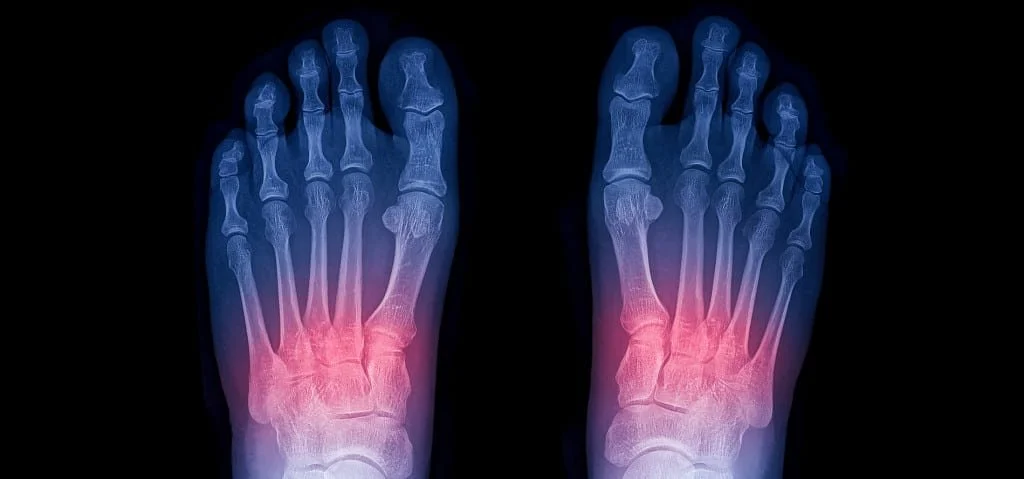

We strive to restore your foot & ankle function using the the least invasive treatment possible so you can get back to on your feet. Dr. Henry uses both nonoperative treatments and surgeries to get you back to doing what you love. These are just some of the procedures Dr. Henry specializes in.

Through a joint decision-making process, we may recommend surgical treatment if we believe the potential benefits outweigh the risks. For patients with chronic (long-term) conditions, the decision for surgery may come after a period of nonoperative treatment, including shoewear changes, orthotics (shoe inserts), ankle/foot braces, physical therapy, medication, activity optimization, and injections. You will discuss this in your consultation with Dr. Henry.